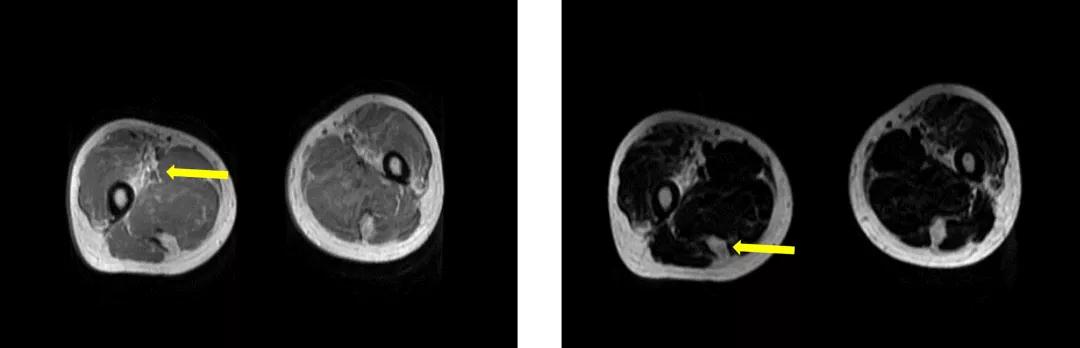

大腿增强MRI:双侧大腿根部、臀肌、盆底肌肉脂肪浸润。

右侧股四头肌活检:骨骼肌呈慢性肌源性肌病改变,不能除外为肌营养不良。

王誉萱博士(病理科)点评:

低倍镜下可见肌束差异性较前次活检更大,肌肉组织被脂肪组织取代;高背景下可见核内移现象,可见大量萎缩肌纤维,以及核固缩聚集现象,膜蛋白免疫组化未见明显异常,提示慢性肌源性肌病改变。上述变化大多数出现在肌营养不良,但具体分型需结合临床及基因检测结果进一步判断。